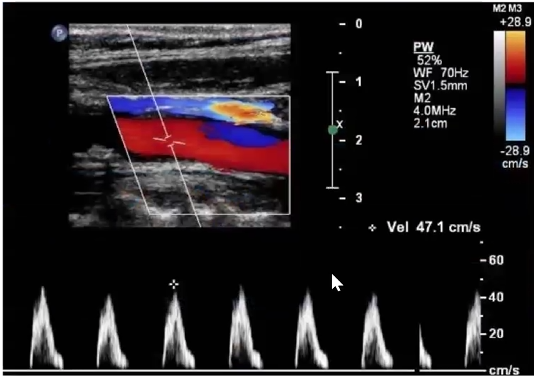

Consider this image.

1. Which vessel is is sample gate positioned?

2. Is the cursor parallel to vessel wall?

3. Is velocity measurement reliable? Why or why not?

4. How would you optimize image? List two items

Rt ICA prox

No

No because the angle is off and its over 60 which will make the velocities higher than they actually are

Decrease depth, move color box up, move sample gate up, fix pw angle, adjust pw ain